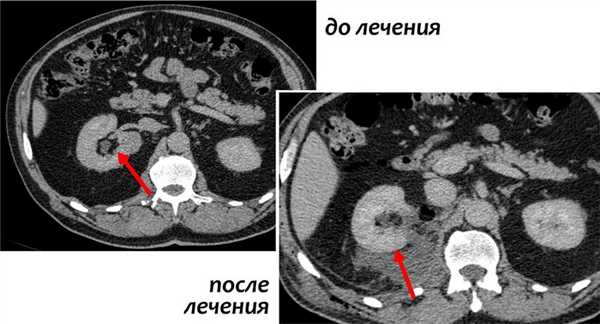

- Томографическое исследование. КТ почки контрастным усилением позволяет обнаружить рак почки любого размера, установить его структуру и локализацию, глубину прорастания паренхимы, инфильтрацию паранефральной клетчатки, опухолевый тромбоз почечной и нижней полой вен. При наличии соответствующих симптомов проводится КТ органов брюшной полости, забрюшинного пространства, костей, легких и головного мозга с целью выявления метастазов.